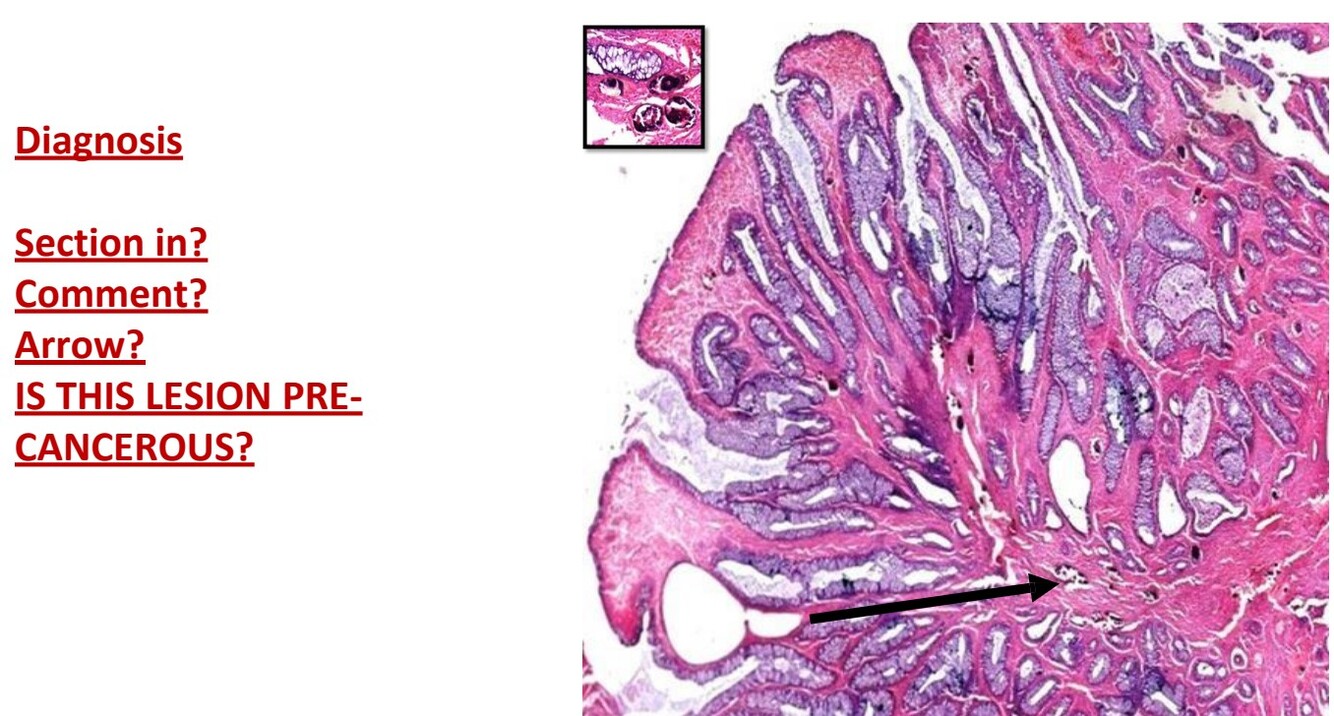

Adenoma (intestine)

Benign tumor formed of proliferated acini lined by columnar mucin secreting cells

Some show pseudo-stratification

Vascular CT is found between gland

precancerous